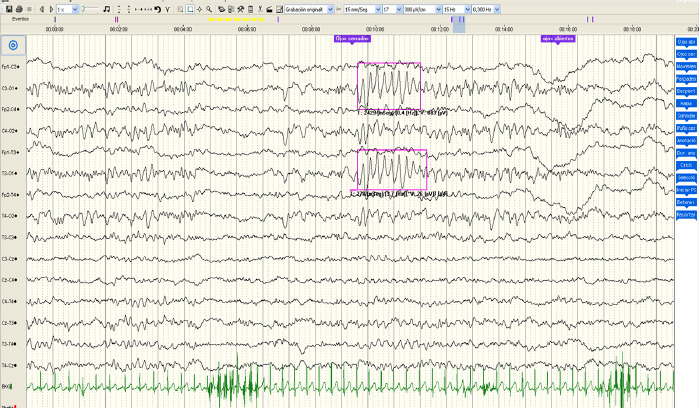

Introduction: Angelman syndrome is a genetic disorder characterised by severe mental retardation, subtle dysmorphic facial features, a characteristic behavioural phenotype, seizures and abnormalities in video electroencephalograms (video EEG). Angelman syndrome may be associated with genetic mechanisms involving the region of chromosome 15q11-13. Up to 90% of cases have epileptic seizures, usually in the early years of life. Videoelectroencephalography patterns with some typical characteristics associated with Angelman syndrome have been reported, although these are not specific to it, and as such it is also useful for early diagnosis, especially in the first months or years of life.

Patients and methods: We conducted a retrospective observational study of 34 video EEGs performed on 17 patients diagnosed with Angelman syndrome at the clinical neurophysiology service of the Puerta de Hierro University Hospital in Madrid between 2019 and 2022. The primary objective was to characterise the videoelectroencephalographic findings and compare them with previously published studies. As secondary objectives, we analysed the patterns proposed by Dan and Boyd, and other demographic, genetic and clinical data.

Results: Video EEG supported the clinical suspicion in our study, as baseline brain activity was altered in all the patients. We identified a pattern similar to those defined by Dan and Boyd in 88% of the cases, and the type III pattern was the most common in our series.